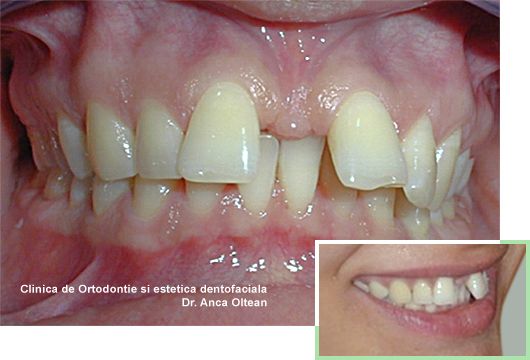

Canin erupt in afara arcadei, inainte de tratament

Canin erupt in afara arcadei, dupa tratament